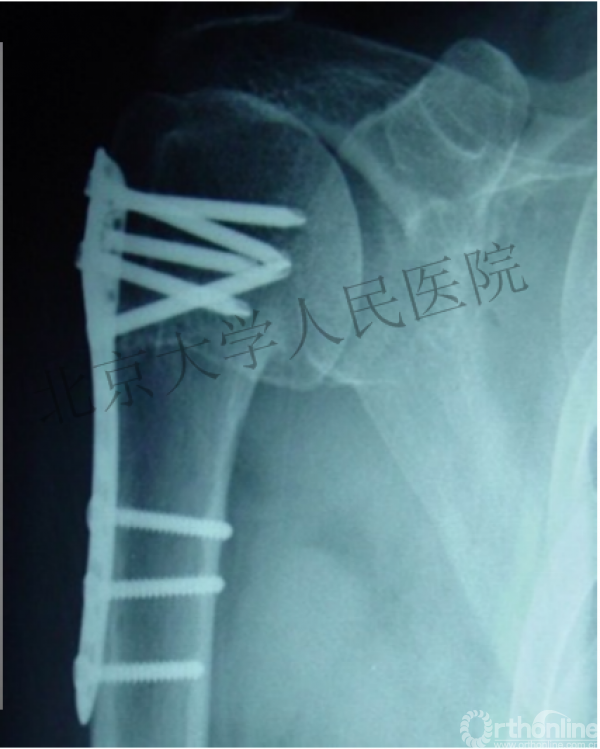

内侧皮质粉碎,低位外科颈骨折,肱骨头-干角维持困难。

术后复位丢失,肱骨头内翻畸形。

能否该偏心固定(钢板)为髓内固定,增加力臂?

早知今日,何必当初?

此时对比髓内钉是不是有很大优势?

另一个留有遗憾的病例,您的选择?PHN?